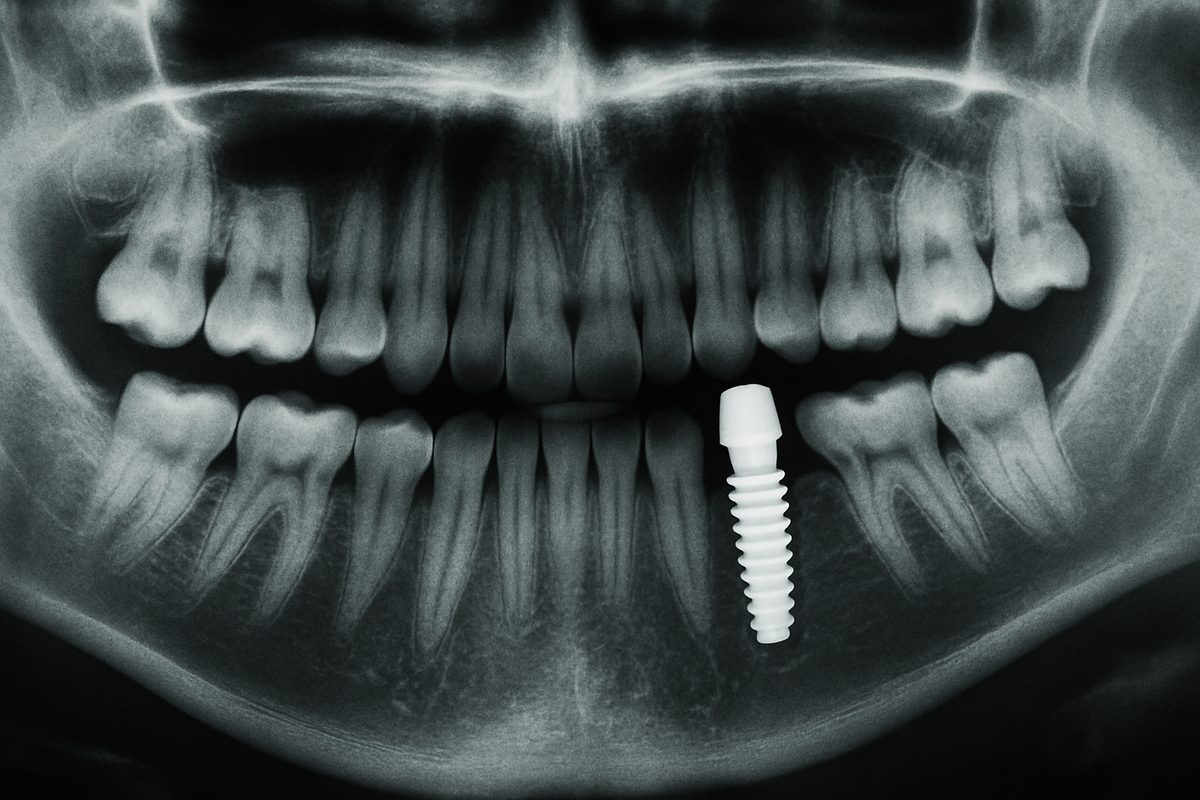

A single dental implant replaces one missing tooth using three parts: the implant (a small titanium post), the abutment (connector), and the crown (the visible tooth). Unlike a bridge, a single dental implant does not require grinding down neighboring teeth. Unlike removable dentures, the implant is fixed in the bone and restores chewing force and speech more naturally. Implants fuse with bone through osseointegration, making them stable and durable.

A small incision is made to place the titanium implant into the jaw using 3D-printed surgical guides for accuracy. Sedation options include nitrous oxide or IV sedation to keep you comfortable. Most single-implant surgeries are quick and well-tolerated.

Osseointegration usually takes several months. If a bone graft was placed, healing may take longer. After integration, an abutment is attached, and a final crown is made. Crowns can be same-day CEREC restorations or lab-fabricated crowns from an in-house lab for optimum fit and esthetics.